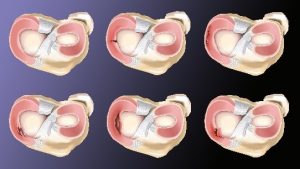

The meniscus is something that many people aren’t familiar with, unless they have had a meniscus tear, then you definitely know all about it. It hurts!

The lateral (outside of knee joint) and medial (inside of knee joint) meniscus cushion the femur (thigh) bone and tibia (shin bone) so your knee can bend and straighten without wearing down the bone.

Trauma to the knee joint, especially a twisting movement, will tear the meniscus.

Trauma to the knee joint, especially a twisting movement, will tear the meniscus.

As a result, when Dr. Cohen told me that my meniscus would heal with scar tissue, I believed him. And it worked! The only glitch was the scar tissue made my knee stiff, so I started to do a movement that I believed would stretch the scar tissue enough so I could bend my knee properly. And that worked too!